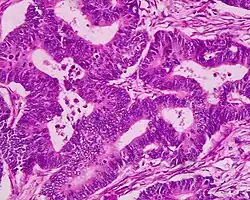

Un adénocarcinome est une tumeur maligne développée aux dépens d'un épithélium glandulaire. Le terme est à distinguer de celui d'adénome qui désigne une tumeur développée aux dépens d'un épithélium glandulaire, mais bénigne. En pratique, une tumeur est reconnue comme adénocarcinome lorsque son analyse microscopique anatomo-pathologique démontre un aspect de glande (tubes glandulaires) ou la présence de sécrétions mucineuses (muco-sécrétions).